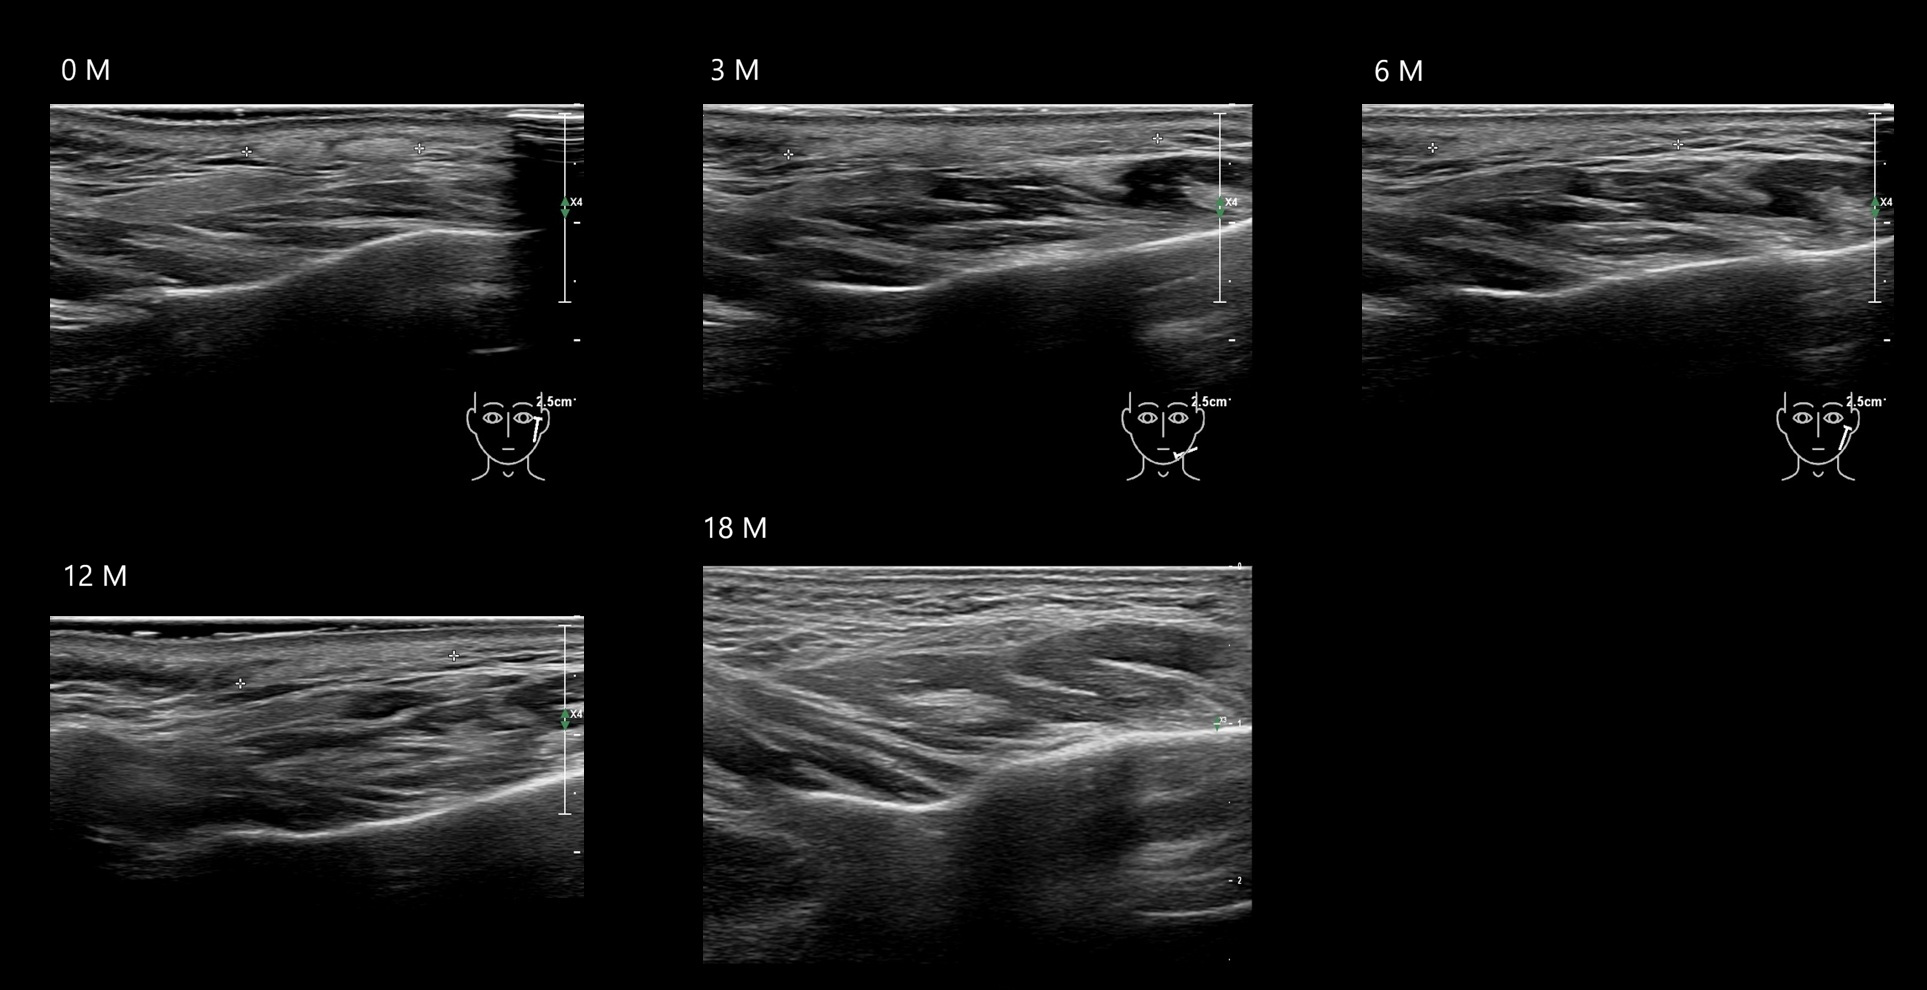

Draw in the image on the right where the fillers are located. To check if your answer is correct, please click on the secondary image.

Fillers